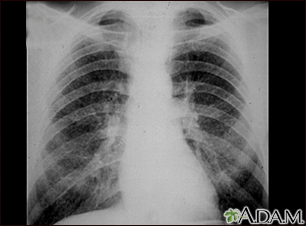

Coal workers pneumoconiosis - stage II